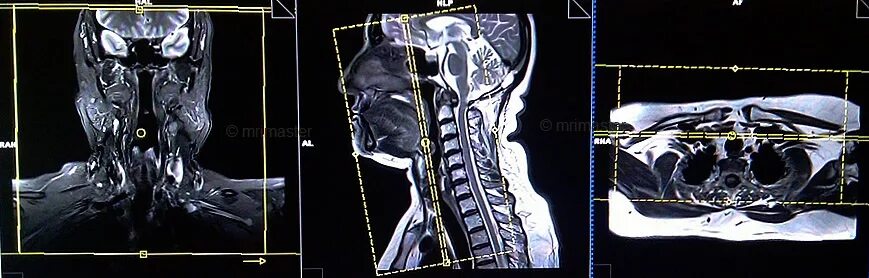

Кт тканей